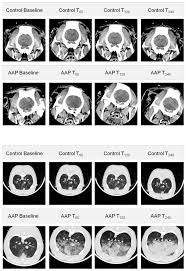

Effects Of Pulmonary Acid Aspiration On The Lungs And Extra Pulmonary Organs A Randomized Study In Pigs Critical Care Full Text

The administration of low doses of albumin was not different than Hartmanns solution but led to the best survival in our model. 1 h before induction of anaesthesia to 20 patients about to undergo emergency surgery.